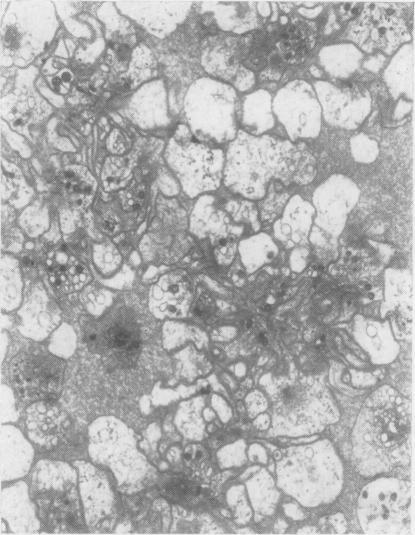

The platelets of a patient with reticulum-cell sarcoma were found to exhibit agglutination and cytopathic changes when her blood was treated with EDTA but not with other anticoagulants. Investigation showed that the phenomenon was caused by a serum factor that was probably an antibody.

当用乙二胺四乙酸(EDTA)处理一名网状细胞肉瘤患者的血液时,发现其血小板出现凝集和细胞病变改变,而用其他抗凝剂处理时则未出现这种情况。研究表明,该现象是由一种可能为抗体的血清因子引起的。